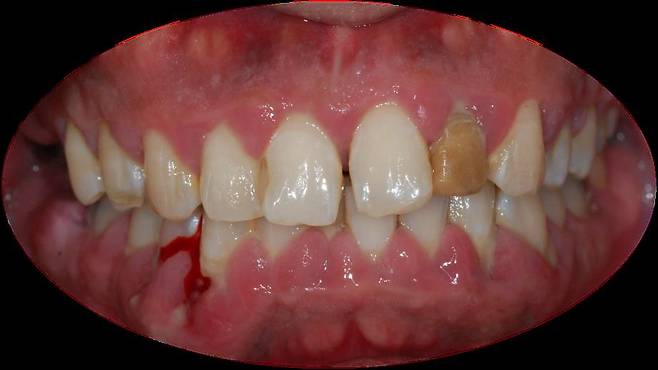

양치할 때, 침을 뱉을 때 피가 비치면 잇몸병을 의심할 수 있다. 이 밖에도 △잇몸에서 피가 난다 △잇몸이 빨갛게 변하거나 붓는다 △잇몸이 주기적으로 들뜨고 근질거린다 △이와 이 사이가 벌어지고 음식물이 많이 낀다 △잇몸이 내려가 점점 치아가 길어 보인다 △나쁜 입 냄새가 난다 △흔들리는 치아가 있다 등 증상이 있다면 잇몸병이 있는지 확인해야 한다.